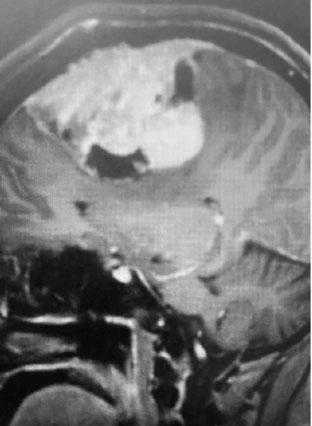

Fig 1. A) Pre-operative, post-contrast, coronal MRI. Arrow points to tumor involvement in the superior sagittal sinus.

This is a 55 year old right-handed woman who was having progressive balance problems. MRI with and without contrast demonstrated a 7 cm partly cystic meningioma involving the left frontal convexity and falx, and encasing the superior sagittal sinus. There was also tumor involvement of part of the convexity skull.

Meningiomas that involve the superior sagittal sinus: Sometimes convexity or falx meningiomas will grow into the superior sagittal sinus. Sometimes the sinus can become completely occluded. Usually this occurs over many years, and as such, the brain has time to develop venous collaterals. So, while in a normal person, sudden occlusion of the superior sagittal sinus could lead to venous infarction or death, the very gradual occlusion that can be seen with meningiomas, does not lead to these problems. Also, if the sinus is filled with tumor and completely occluded, it can usually be safely removed at that segment.

Convexity and Falx Meningiomas: While meningiomas can involve either the convexity or the falx alone, it is possible for such tumors to involve both structures. In this case, vascular supply to the tumor can originate from both dural sources. When meningiomas involve the convexity dura, the dura is often excised and replaced with a duraplasty (an artificial dural replacement). When tumors involve the falx, the falx itself is usually not removed in entirety.